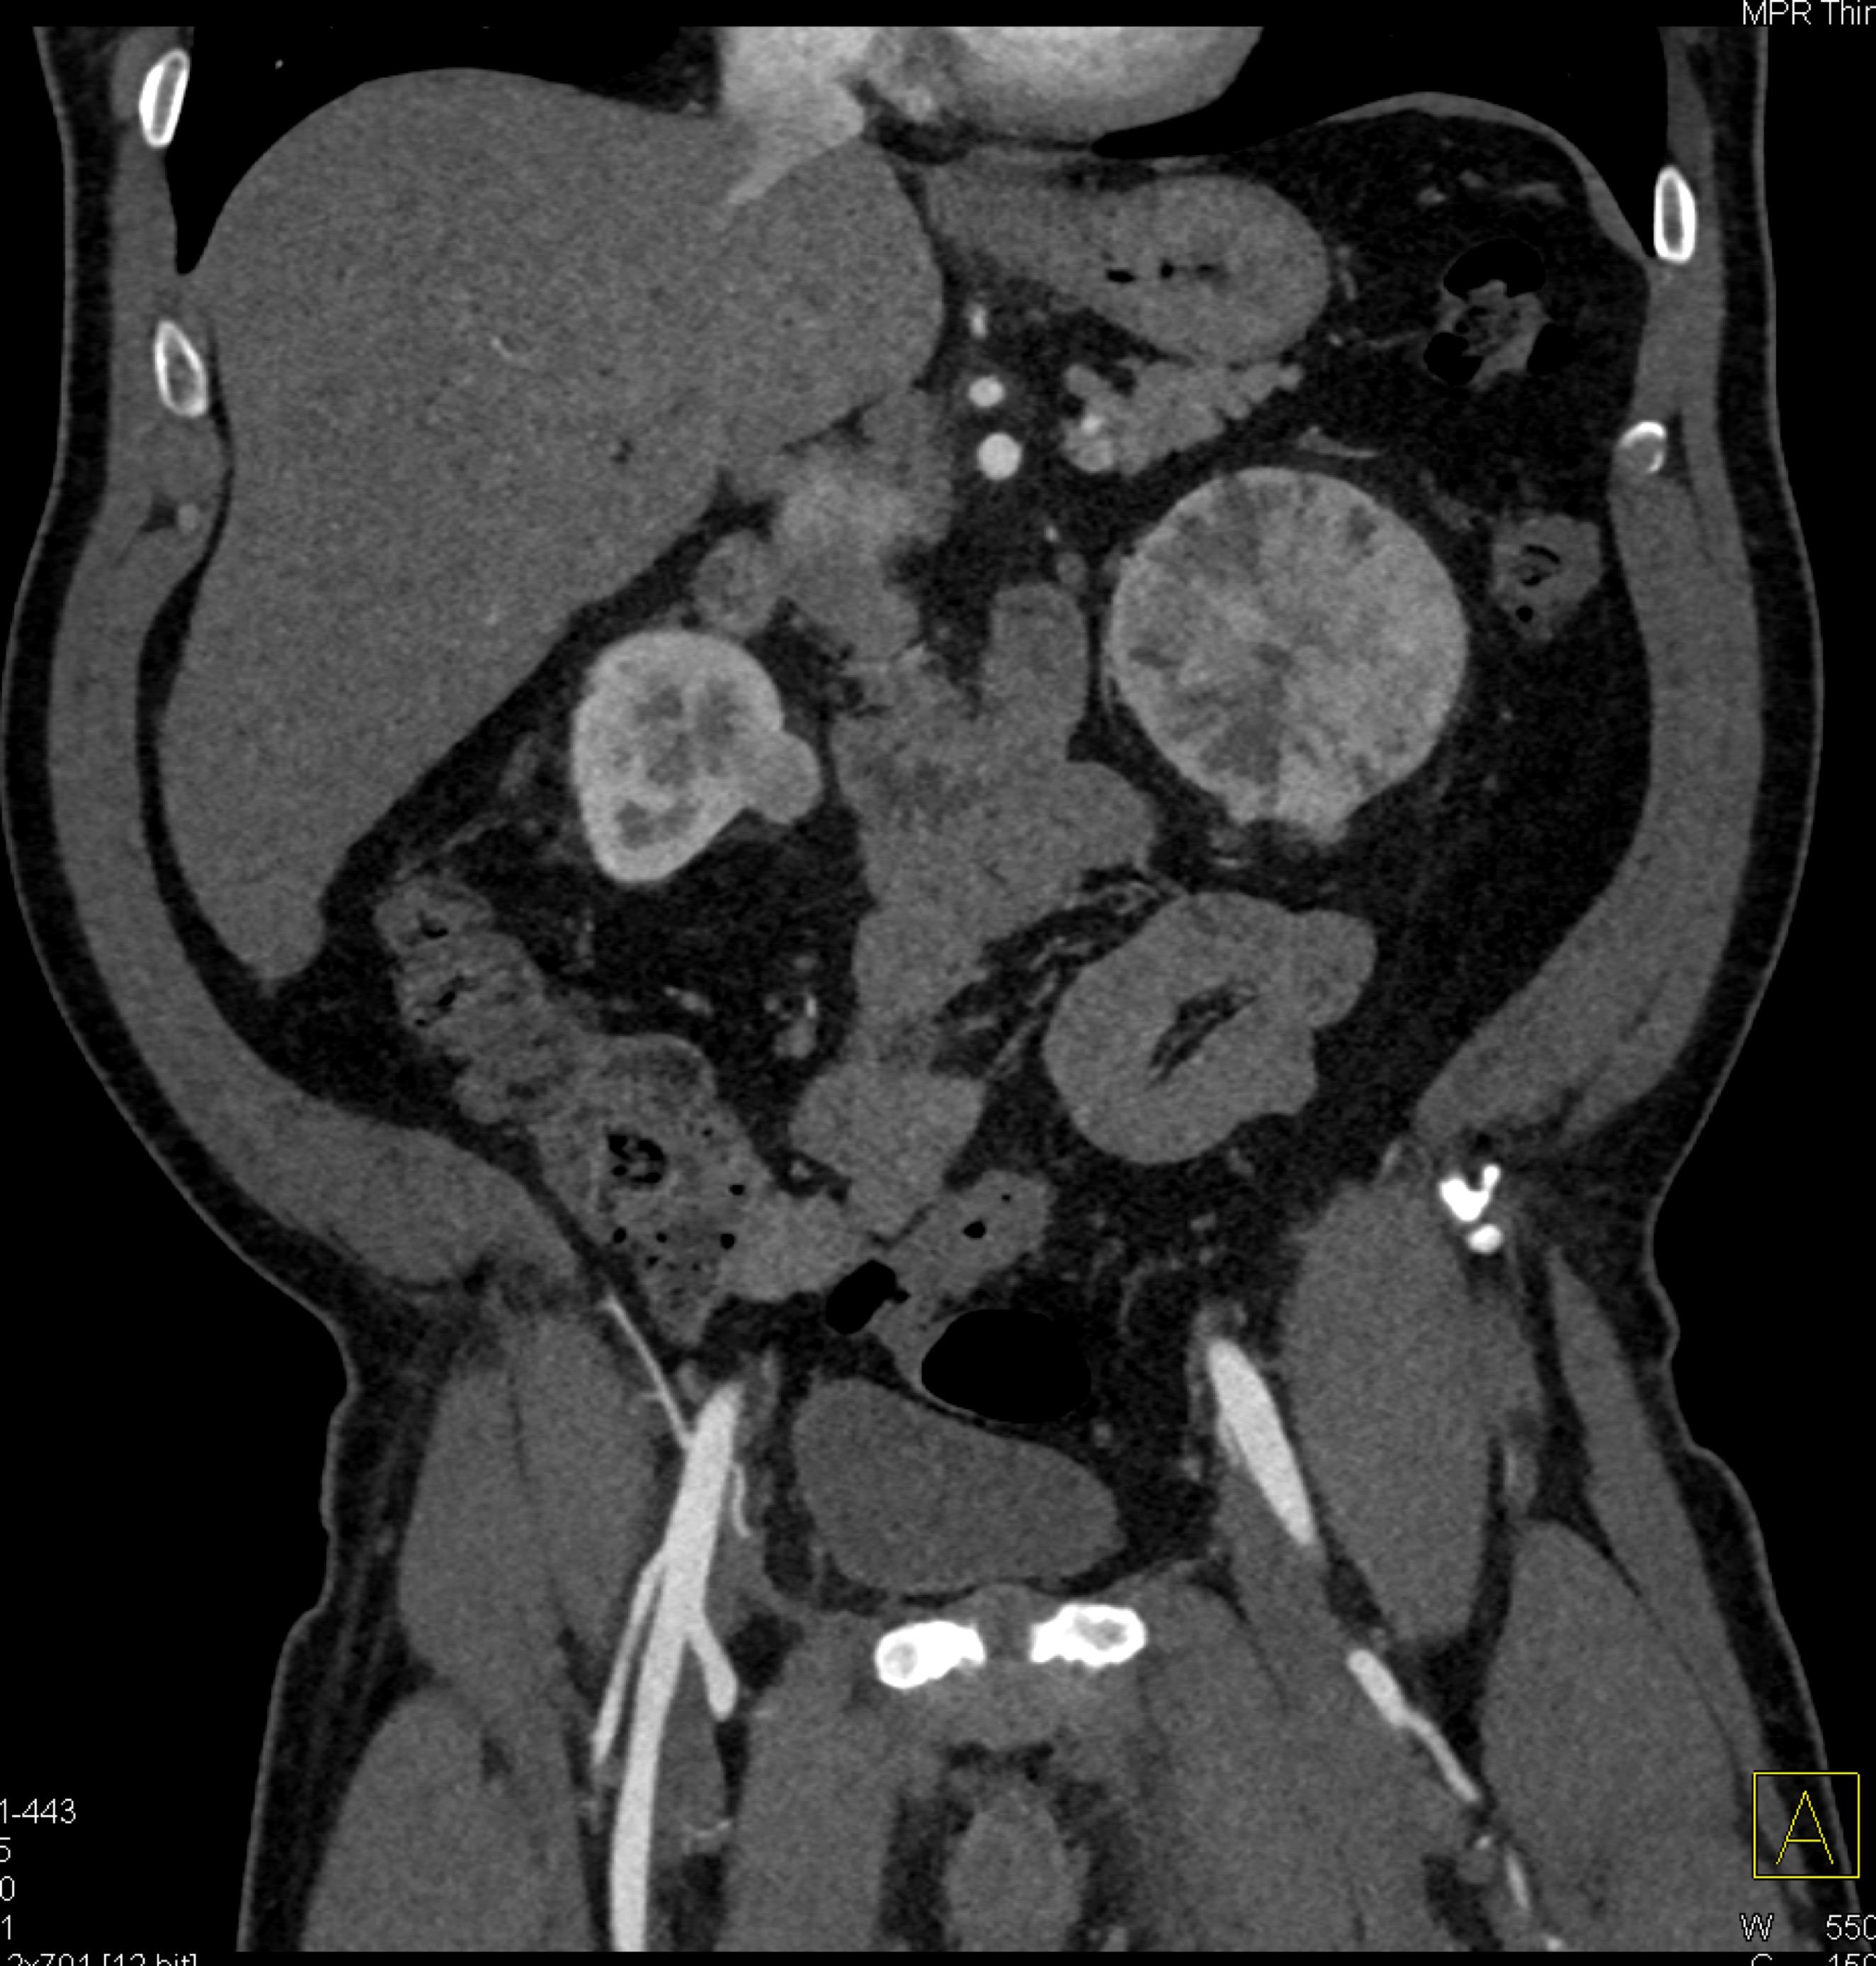

8) The most likely diagnosis for the dominant left renal mass is?

clear cell renal cell carcinoma

metastatic melanoma

papillary renal cell carcinoma

renal oncocytoma